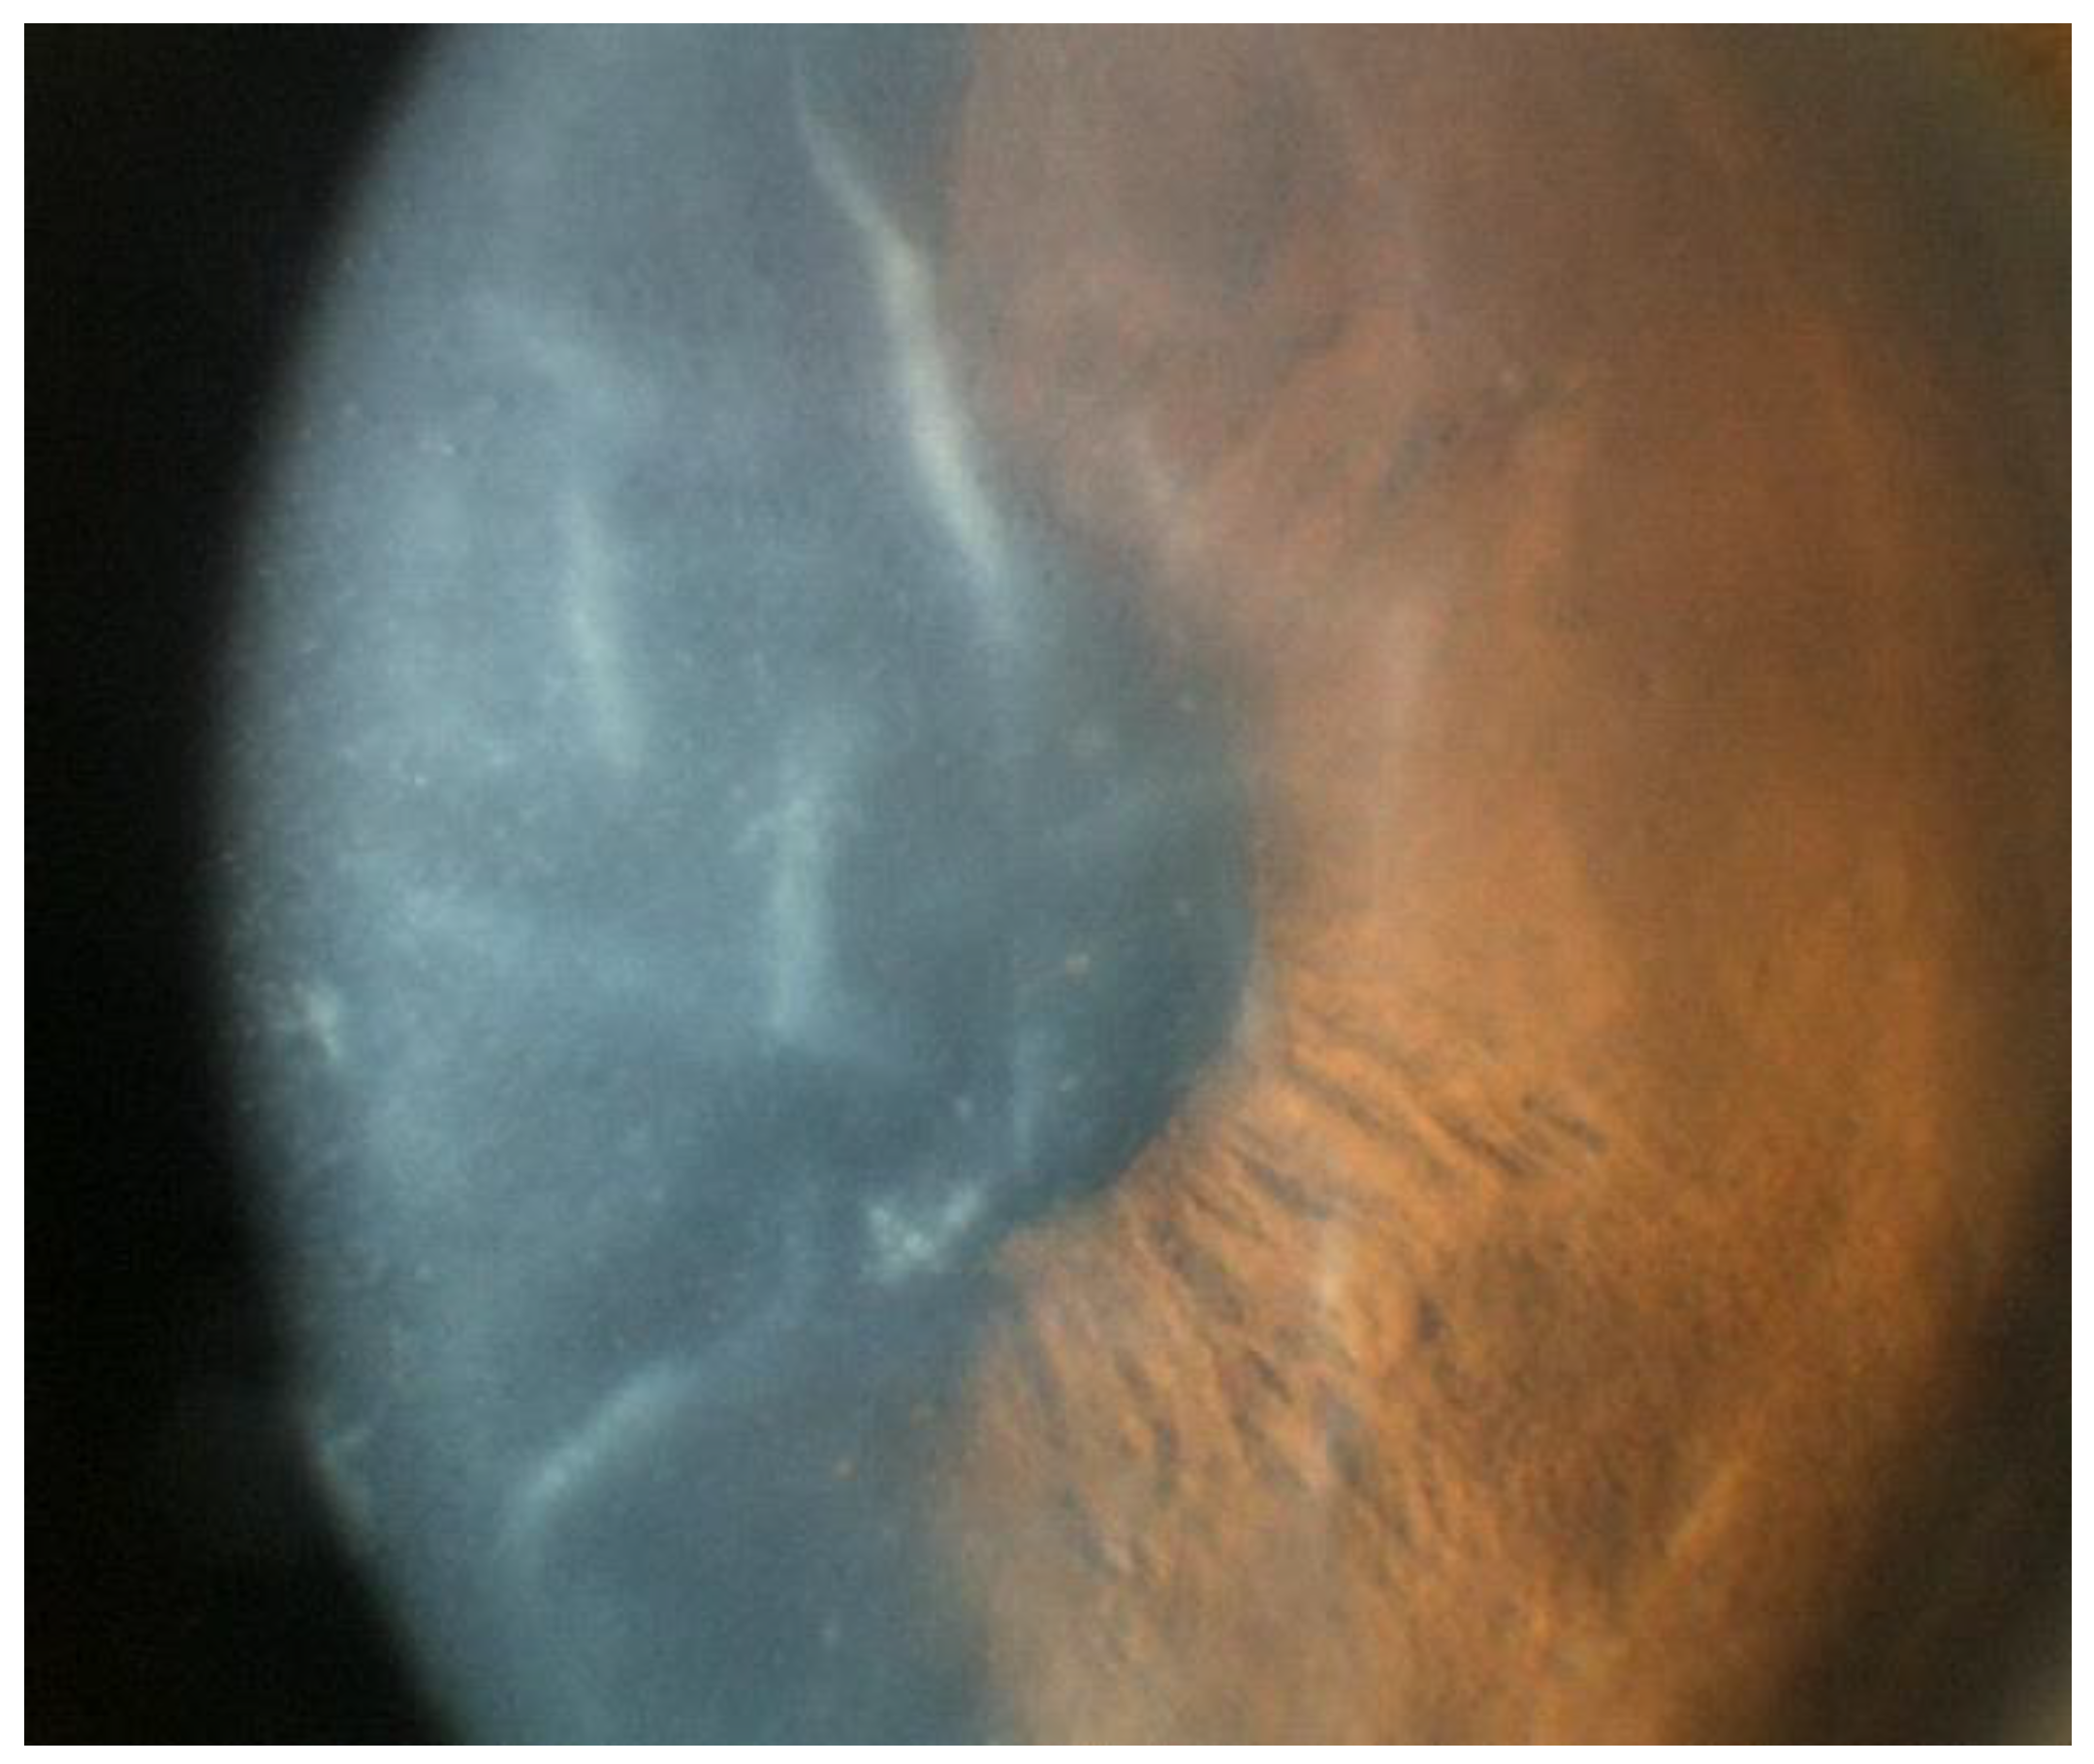

Unique from other viral entities, VZV reactivation is associated with a vesicular eruption on the periocular skin and eyelid along the V1 distribution [52]. Corneal endotheliitis usually presents within 1 month of onset of the painful rash and is preceded by the development of punctate epitheliopathy and pseudodendrite formation, which typically occur within 10 days of skin involvement [54]. Some patients may also develop prolonged epithelial keratitis similar to HSV-associated cases, but in contrast to HSV dendritic keratitis, pseudodendrites in VZV usually lack terminal bulbs and stain poorly with fluorescein and rose bengal (Figure 5) [54].

As with other etiologic variants of viral endotheliitis, the most commonly reported symptoms include photophobia, conjunctival injection, and decreased visual acuity unilaterally [52,55,56,57,58,59]. Manifestations of VZV endotheliitis following the onset of the dermatomal rash include the onset of corneal edema, keratic precipitates, and Descemet folds within 4–7 days (Figure 6) [54]. Similar to CMV and HSV, the corneal edema and KPs are most commonly found in a disciform pattern [52,55,56] but can also manifest diffusely [60], sectorally, or linearly [60]. In comparison with HSV-associated endotheliitis, cases secondary to VZV usually present with a more severe anterior chamber inflammation, with a greater chance of developing a hyphema or hypopyon [6,57,58,59]. Finally, as is the case with CMV and HSV, VZV has also been implicated as a cause of endotheliitis following keratoplasty [60].

Figure 6.

Slit lamp photos of two patients with VZV endotheliitis. (A) Diffuse KPs and disciform corneal edema (black arrow) in VZV endotheliitis. (B) Disciform corneal edema (white arrow). ((A) courtesy of EyeWiki (San Francisco, CA, USA); used with the permission of the publisher [64]).